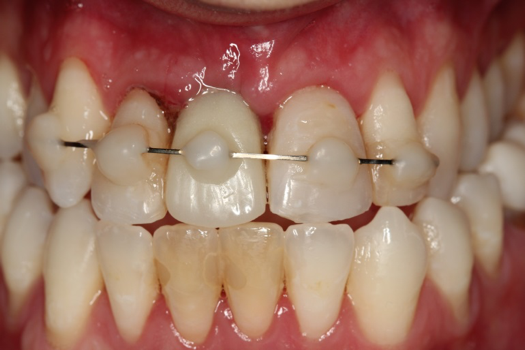

Case 3. TRAUMA: SINGLE Central INCISOR-GUIDED Smile

A 23-year-old man reported to the dental practice on January 3. Apparently, while on vacation and celebrating the New Year, the patient experienced a loss of equilibrium and found himself horizontal in the crosswalk. When surveying the damages, his friends noticed he was missing tooth No. 8. Those who were involved were not able to find the missing maxillary central incisor. The young man was eventually seen about 3 days after the trauma. A CBCT radiograph, study models, and photographs were collected, and teeth Nos. 6 through 10 were immobilized with composite and 20 x 20 orthodontic wire (Figure 14). The CBCT and photos were emailed to the dental laboratory, and the analog intraoral impression with a centric occlusion bite registration was sent via ground transportation. Due to the nature of the trauma, the laboratory and the author expeditiously converted the analog diagnostics and merged all the patient's data sets to develop the plan. Based on the 3D data sets, the laboratory and the dentist were able to accurately assess the volume of bone and soft tissue remaining after the trauma. The volume was still intact and soft tissue was plentiful (Figure 15 and Figure 16).

The provisional abutment and treatment crown were fabricated in the laboratory with the digital proposals. Platelet-rich fibrin (PRF) clot technology was incorporated to help with soft- and hard-tissue healing (Figure 19 through Figure 21). The screw-retained provisional and the PRF clot were seated immediately after implant placement (Figure 22 and Figure 23). One 4-0 polytetrafluoroethylene suture was placed to maintain papilla. The teeth immobilization splint was placed for 6 weeks (Figure 24). The rationale for splinting teeth Nos. 6 through 10 was due to noticeable plus-2 mobility of the remaining anterior teeth. The provisional implant crown also was included in the splint.

Fig 14. Immobilization splint placed 3 days after trauma.

Figure 14

Fig 24. Immobilization splint placed after surgery, to be worn for no more than 6 weeks.

Figure 24